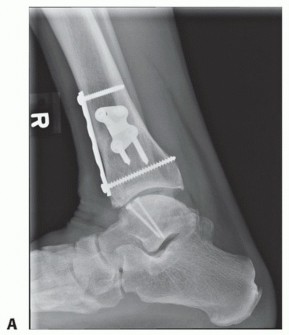

- TECH FIG 1 • A. Medial incision and anterior ankle arthrotomy. B. Opening of the posterior tibial tendon sheath. C. Predrilling of medial malleolus. Kirschner wire for trajectory of medial malleolar osteotomy has already been inserted and its position confirmed with fluoroscopy. D. Fluoroscopic image demonstrating Kirschner wire being used as a guide to direct the saw. E. The periosteum is scored perpendicular to the tibial shaft, at the level of the osteotomy. F. Medial malleolar osteotomy. Care must be taken to protect the posterior tibial tendon. (continued)

- TECH FIG 1 • (continued) G. Fluoroscopic image showing near-complete bone cut. H. Release of posterior tibial tendon sheath from distal medial malleolus to allow mobilization.

- TECH FIG 4 • (continued) D,E. A different patient with similar graft, excellent interference fit, and secured with a single screw. D. Screw is inserted in lag fashion. E. Screw head is countersunk. F-H. Reduction of the medial malleolar osteotomy. F. Screw fixation through the predrilled holes. G. Antiglide plate. H. Final fluoroscopic evaluation of graft and reduction of medial malleolar osteotomy. Despite optimal clinical fit of the graft, rarely does the fluoroscopic appearance suggest anatomic graft match to the native talus, typically due to differing cartilage thicknesses between the donor and the host. Although the screws may appear prominent, two-dimensional fluoroscopy is deceiving because the screws are countersunk below the articular surface of the graft and the talar dome is curved.